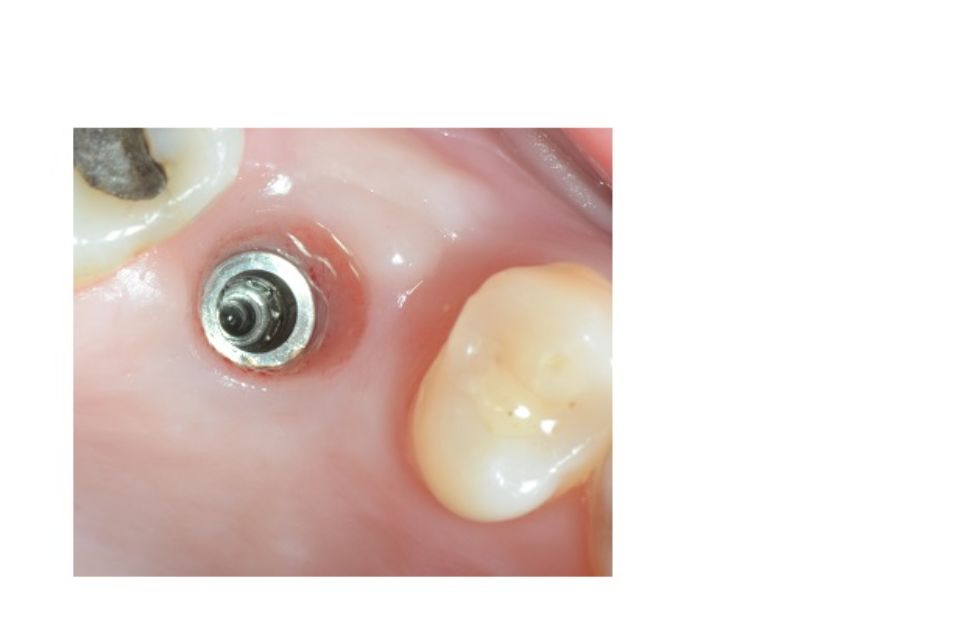

Implantology is the dental specialty that deals with the replacement of the root of the lost tooth.

The replacement is done through a small surgical procedure to place a piece of titanium inside the jawbone.

The implant has a thread inside where the abutment that will support the prosthetic crown will later be screwed on.